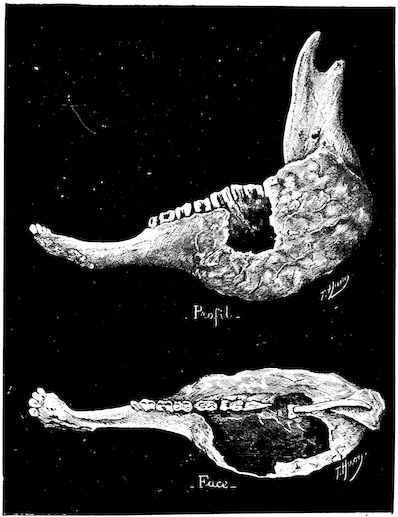

Fig. 4.—Deformity of the face in the horse shown in Fig. 2.

The flat bones are particularly liable to this change, which is common to domesticated animals. The bones of the head are the first to suffer; later those of the pelvis. The lower jaw becomes swollen, particularly about the centre of the branches which may attain three, four, or five times, their normal thickness.

The depression in the submaxillary space disappears. The upper jaw undergoes similar changes, becoming deformed and thickened until the cavities of the sinuses and the hollow appearance of the palate are lost, while the face is so changed that it cannot be recognised as that of a horse, goat, etc.

The molar teeth are almost buried, their tables alone being visible at the bottom of a depression, the edges of which rise above the neighbouring parts (pig).

Mastication is clearly impossible, the jaws appear paralysed, the muscles powerless, and only swallowing is possible, a fact which explains why life is only prolonged to this stage in animals which can be fed with a spoon or bottle (pigs and goats). The bones of the cranium, although greatly changed in texture, are always less deformed than those of the face.

The changes are such that it is often easy with a mere post-mortem knife to cut the head completely in two. Osseous tissue, properly so-called, has disappeared.

Fig. 5.—Head of a pig suffering from osseous cachexia.

Fig. 7.—Osseous cachexia: softening of the maxillæ.